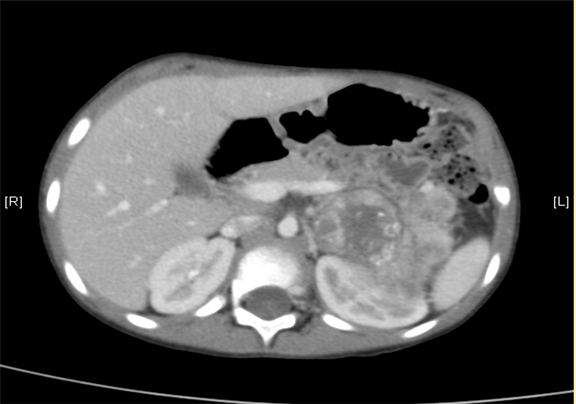

下腹部增强CT示:神经母细胞瘤。

将0.625mm双源薄层CT资料的静脉期和动脉期Dicom格式文件导入海信CAS系统。

通过调节窗宽窗位调整CT序号,对肿瘤,肝实质,胆囊,下腔静脉,肿瘤,肝动脉、门静脉及肝静脉等进行三维重建;系统自动计算肿瘤体积和肝脏体积。

术前CT检查:

动脉期